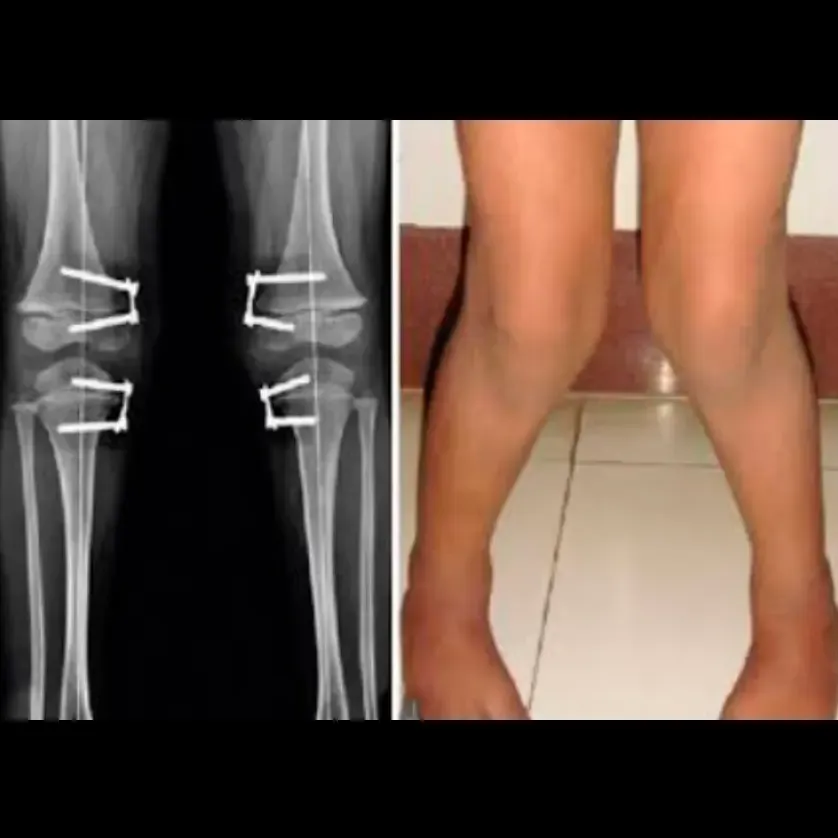

Luxación de rótula / inestabilidad patelofemoral

La rótula se desplaza o se luxa hacia la parte lateral de la rodilla, fuera de su posición habitual, causando dolor intenso e inestabilidad….

Procedimientos: Realineación quirúrgica o estabilización de la rótula con artroscopia.

Realineación rotuliana / liberación lateral

Descripción: Corrección del seguimiento anormal de la rótula.

Indicado para:

• Inestabilidad patelofemoral o luxación recurrente.